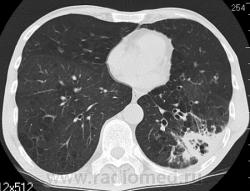

КТ - ОГК.  Ваше мнение коллеги?

На фоне консолидации полость без содержимого. Может быть всё что угодно, что сопровождается деструкцией. Нужны ещё томограммы в лёгочном окне.

Изображения выставлены все. Ваше мнение уважаемые коллеги?

Туберкулёз.

Туберкулёз?